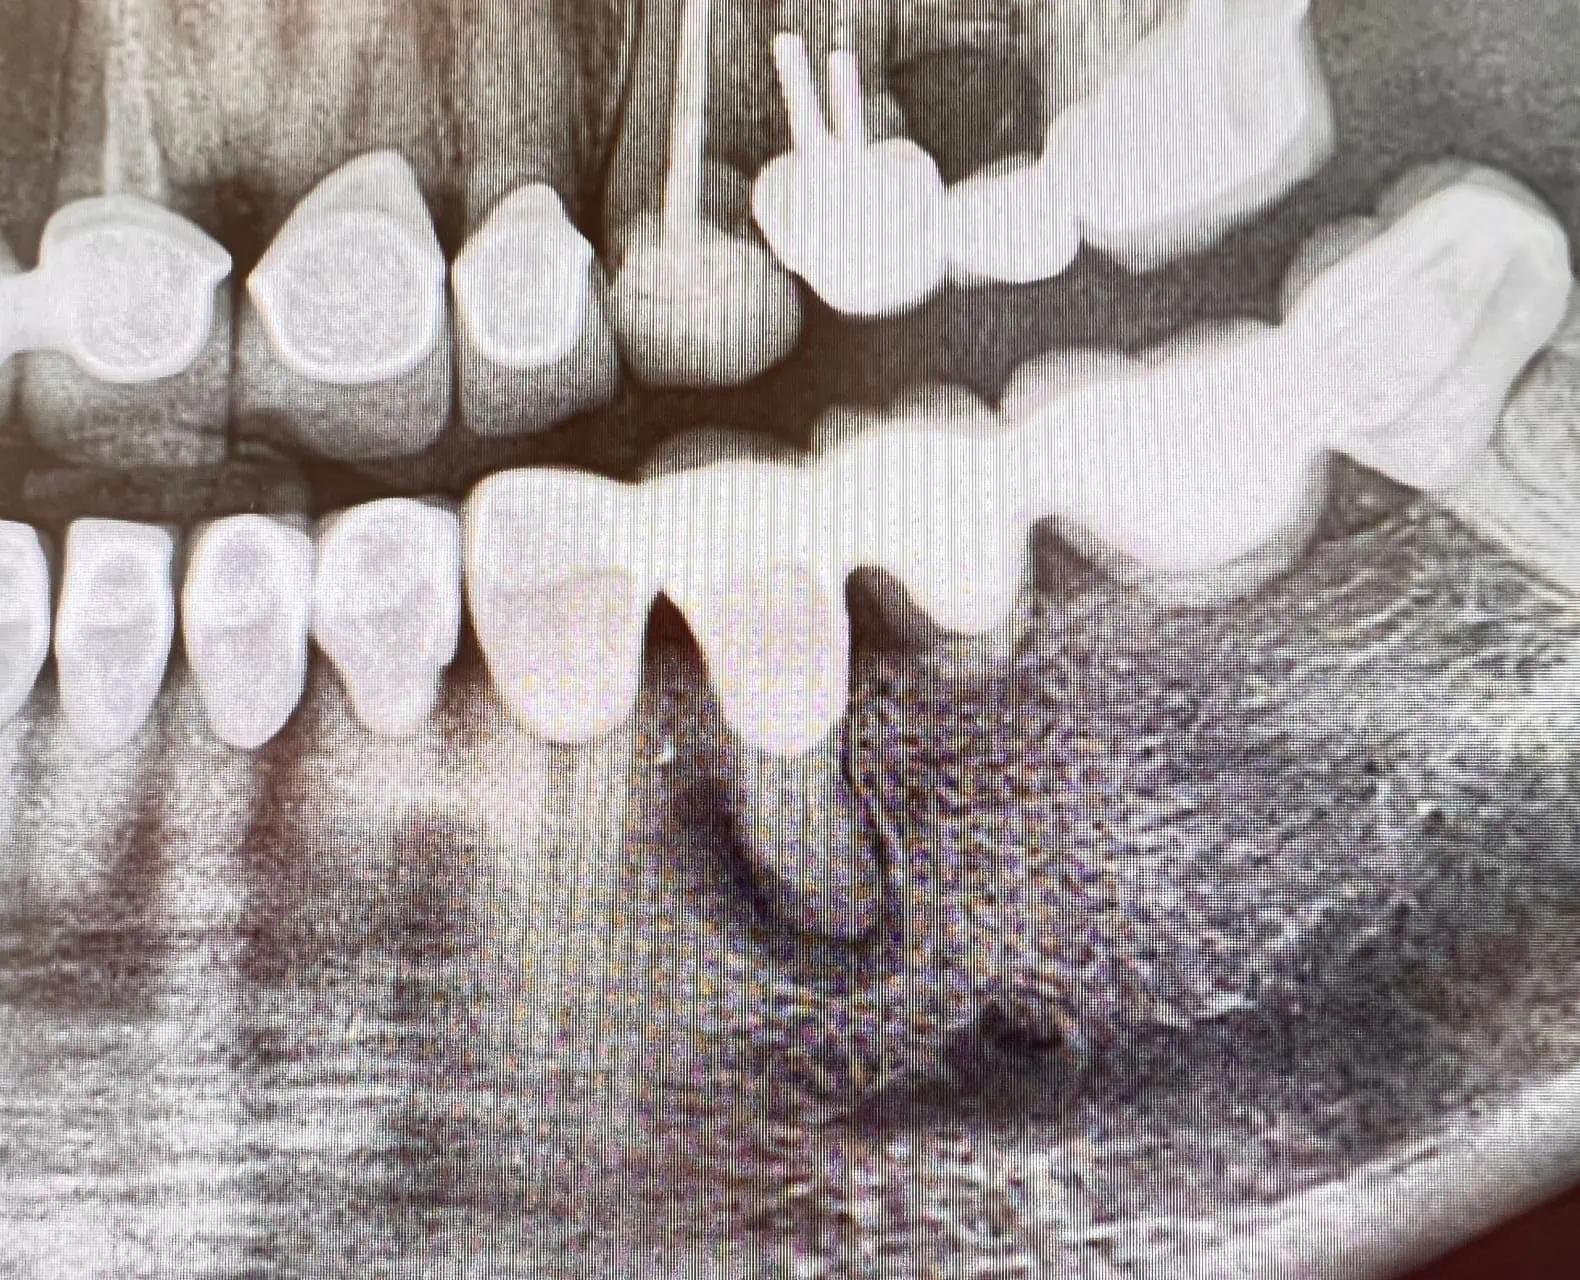

Wurzelbehandlung mit OPMikroskop Endodontie Bad Mergentheim • Zahnarztpraxis Dr. Andreas Kanev. Hinzu kommt, dass wurzelbehandelte Zähne anfälliger für Bakterien sind, als gesunde Zähne Dies hängt von verschiedenen Faktoren ab, wie dem Zustand der Krone und des darunterliegenden Zahnes nach der Wurzelbehandlung.

Ein Zahnbruch kann dazu führen, dass der Zahn letztlich entfernt werden muss, was in den meisten Fällen eine aufwendige und kostenintensive Versorgung mit Zahnersatz wie einem Implantat oder einer Brücke nach. Dies hängt von verschiedenen Faktoren ab, wie dem Zustand der Krone und des darunterliegenden Zahnes nach der Wurzelbehandlung. Auch ein bereits wurzelkanalbehandelter Zahn mit Krone kann Schmerzen bereiten, wobei die Ursache meist eine Entzündung im Bereich der Wurzelspitzen ist.